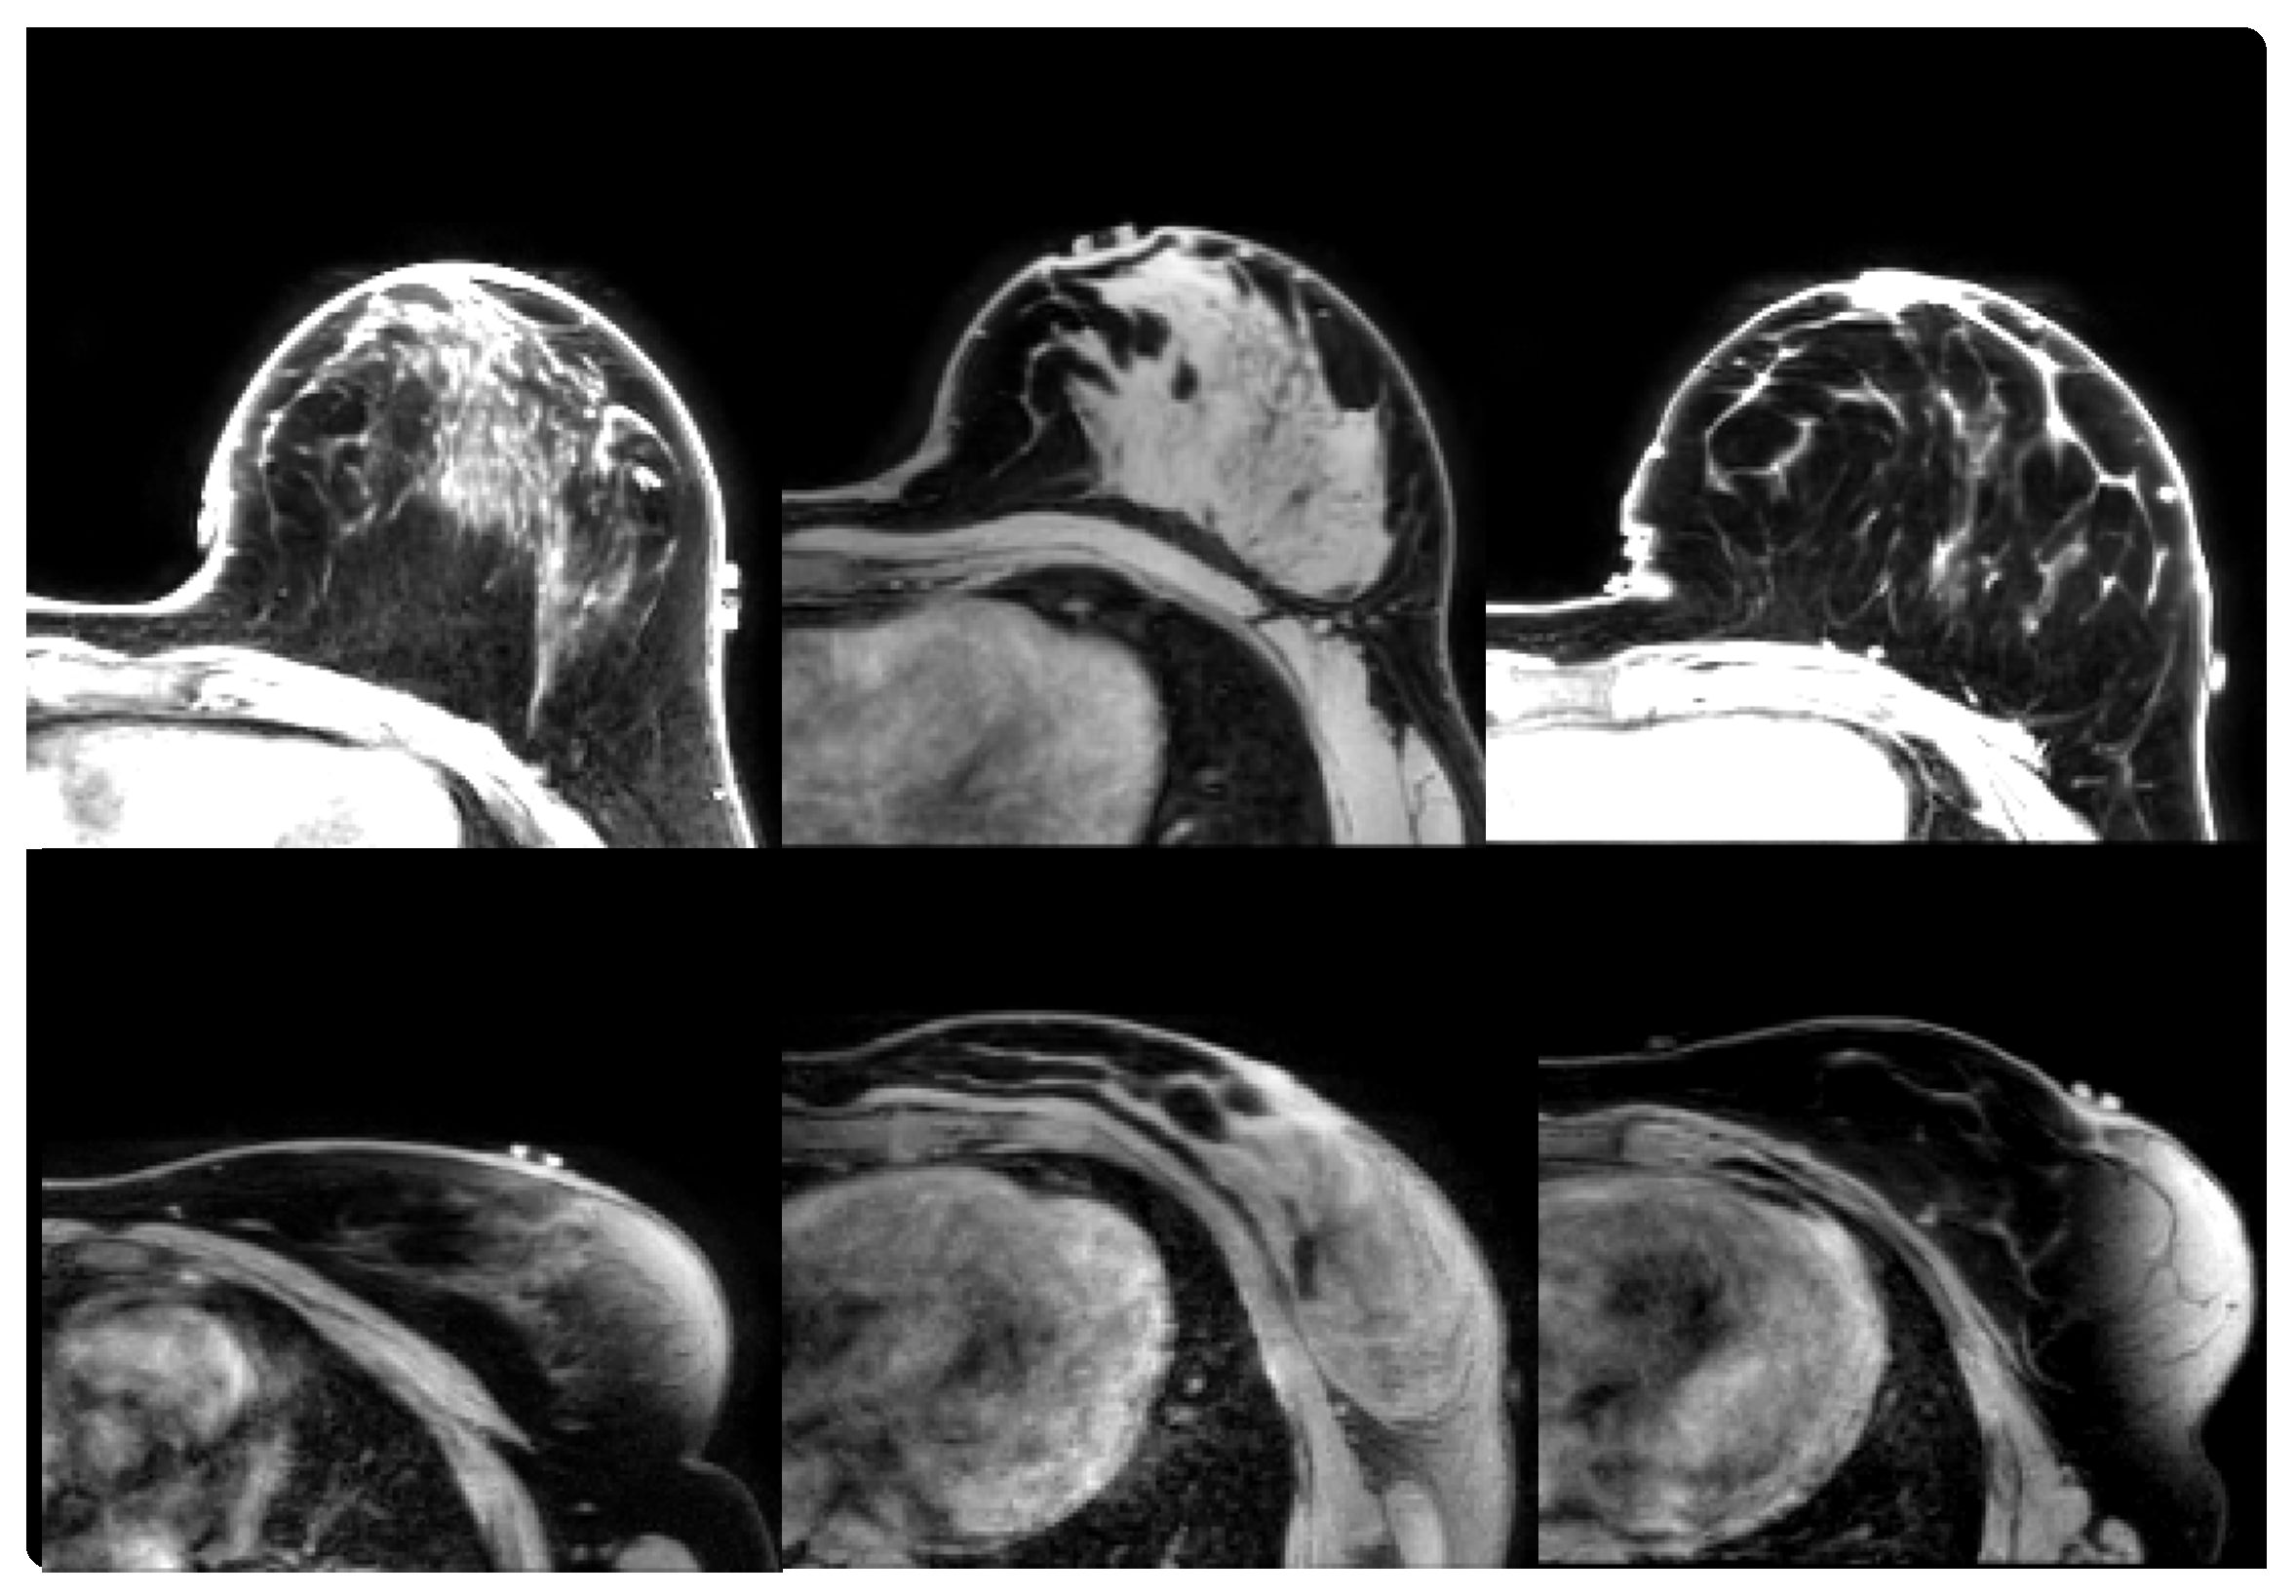

2.1.1. Prone-Prone

2.1.2. Prone-Supine